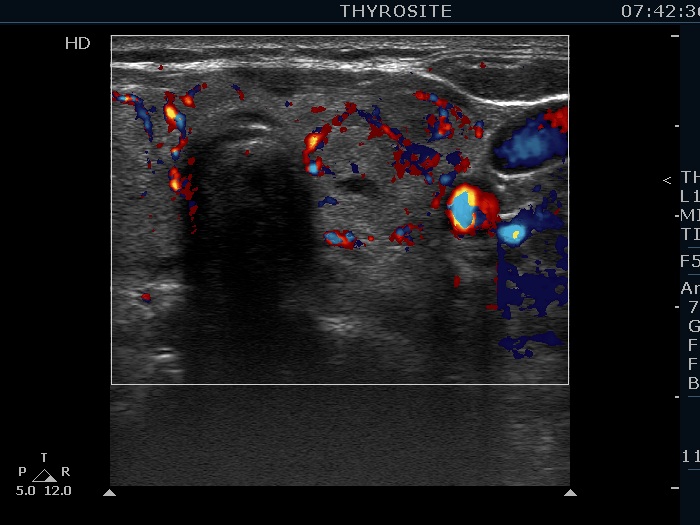

Intranodular hyperechogenic figures - case 155

Three years after the previous examination (ultrasonographic picture 9)

Lower part of the left lobe, trasnverse view, color Doppler mode. Perilesional blood flow is demonstrated.